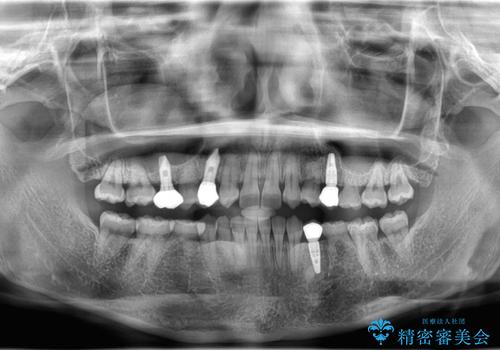

- 後続永久歯が欠損した患者様です。

矯正治療にて歯並びを改善したのち、インプラントにて咬合回復を行う治療計画としました。

捻転が強い部分だけはワイヤーの部分矯正で対応しております。